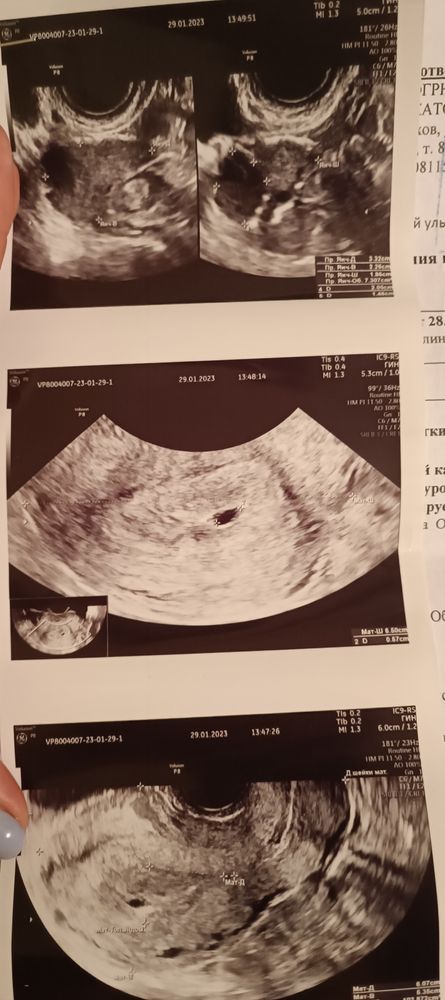

Enotik Lesnoy , Изображение

Илона, как по мне это 100% пя в матке, скоро желточный появится, чем ей не нравится то??

Илона, ну тут по снимку пя в матке

Екатерина Карпова, а может это оно и было которое 20х15 мм непонятно что и мне просто не очень хороший врач УЗИ попался?

Илона, поэтому и говорю, переделайте на другом аппарате. Но блин, если это оно то насколько надо быть глупым врачом, чтобы назвать такой приличный размер (20*15) образованием.🤦‍♀️

По снимкам ПЯ, однозначно, но при таком размере должно быть видно хотя бы ЖМ... Очень похоже на неразвивающуюся беременность

По тому что вы приложили в комментариях, пя в матке, почему узист говорит так неуверенно, не понятно Х))